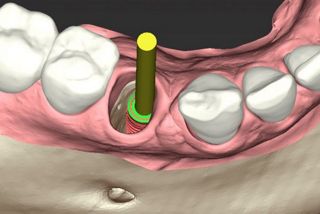

Abb. 2 - Prothetisch orientierte Rückwärtsplanung mit einem KI-Assistenten für die virtuelle Zahnextraktion (CoDiagnostiX) und Simulation der Implantatinsertion (Straumann® BLX 3,75 x 12mm).

Abb. 3 - Digitales Design der chirurgischen Implantatführung (CoDiagnostiX) für die vollständig geführte statische computerunterstützte Implantatchirurgie [sCAIS].